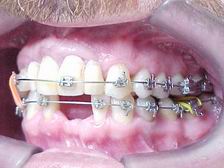

Metalocerâmica sobre implantes (CONCLUÍDO)